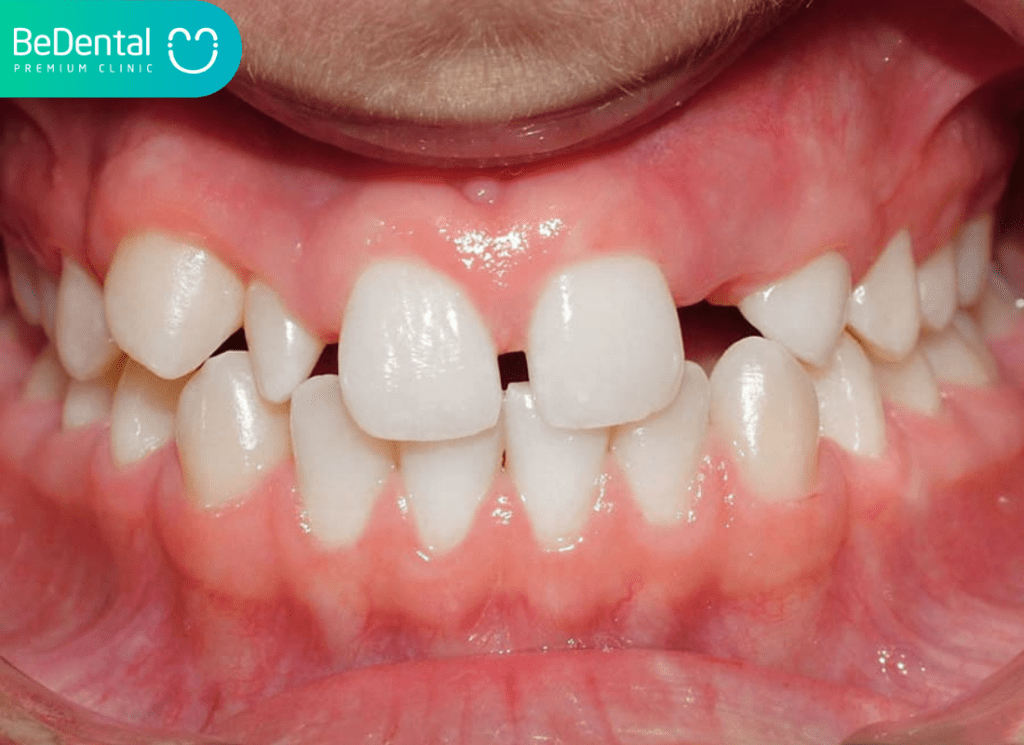

Khi một chiếc răng không mọc, khoảng trống trên hàm sẽ gây mất cân đối. Nghiêm trọng hơn, do thiếu sự nâng đỡ từ răng, các răng lân cận có xu hướng dịch chuyển và đổ nghiêng vào khoảng trống đó, khiến toàn bộ hàm răng trở nên lệch lạc, thưa thớt và khấp khểnh.

Khoảng trống do thiếu mầm răng làm mất đi sự liên kết liên tục giữa các răng. Điều này dẫn đến sai lệch khớp cắn, gây khó khăn cho việc ăn nhai, phát âm và lâu dài có thể dẫn đến các cơn đau khớp thái dương hàm.